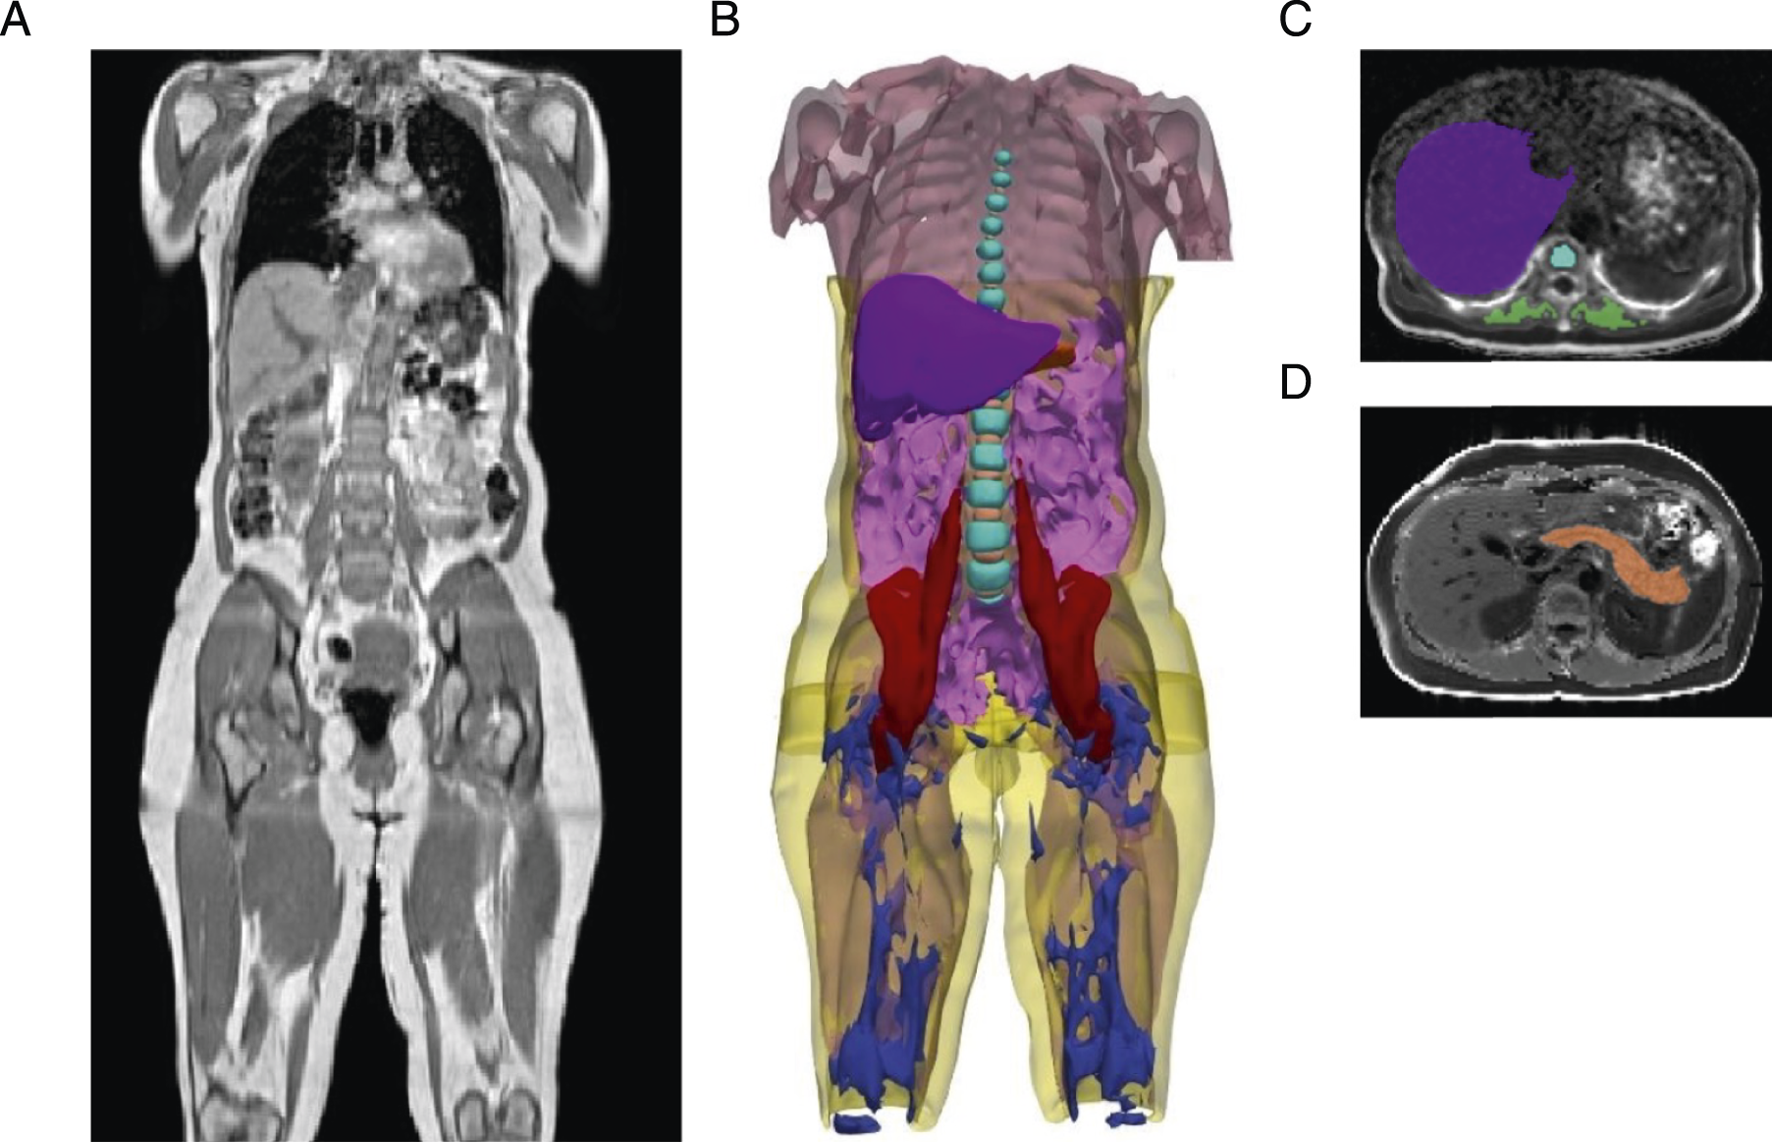

This study utilizes non-invasive abdominal and neck-to-knee MRI techniques in a population-based cohort to quantify 20 IDPs relevant to type 2 diabetes (n = 44,646). These imaging traits include precise measures of fat in seven anatomical locations (visceral, subcutaneous, liver, pancreas, thigh, paraspinal muscle, and vertebral bone marrow), pancreas volume, skeletal muscle volume and skeletal muscle quality, and fatty acid composition in visceral and abdominal subcutaneous adipose tissues (Figure 1; Table 1). Baseline demographic and clinical characteristics of the study population are summarised in Supplementary Table S1. Pairwise covariance analyses revealed moderate but incomplete correlations across IDPs (Supplementary Figure S1).

Figure 1

Figure 1. Segmentation of adipose tissue depots, internal organs, and muscles from deep learning of abdominal MRI scans. (A) Representative three-dimensional MRI acquisition of the abdomen, extending from the neck to the knee. (B) Organs segmented from deep learning models: visceral adipose tissue (magenta), subcutaneous adipose tissue (yellow), liver (purple), pancreas (orange), total muscle (light pink), iliopsoas muscle (red), vertebral bone marrow (cyan blue), intervertebral discs (light orange), thigh intramuscular adipose tissue (IMAT) (dark blue). (C) Representative two-dimensional MRI acquisition of the liver (purple) with vertebral bone marrow (cyan blue), and paraspinal muscle (green). (D) Representative two-dimensional MRI acquisition of the pancreas (orange).